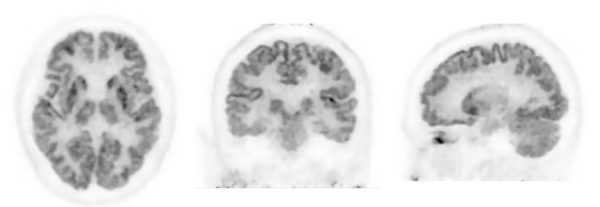

写真:頭部FDG-PET画像

(データ提供:近畿大学高度先端総合医療センターPET分子イメージング部)